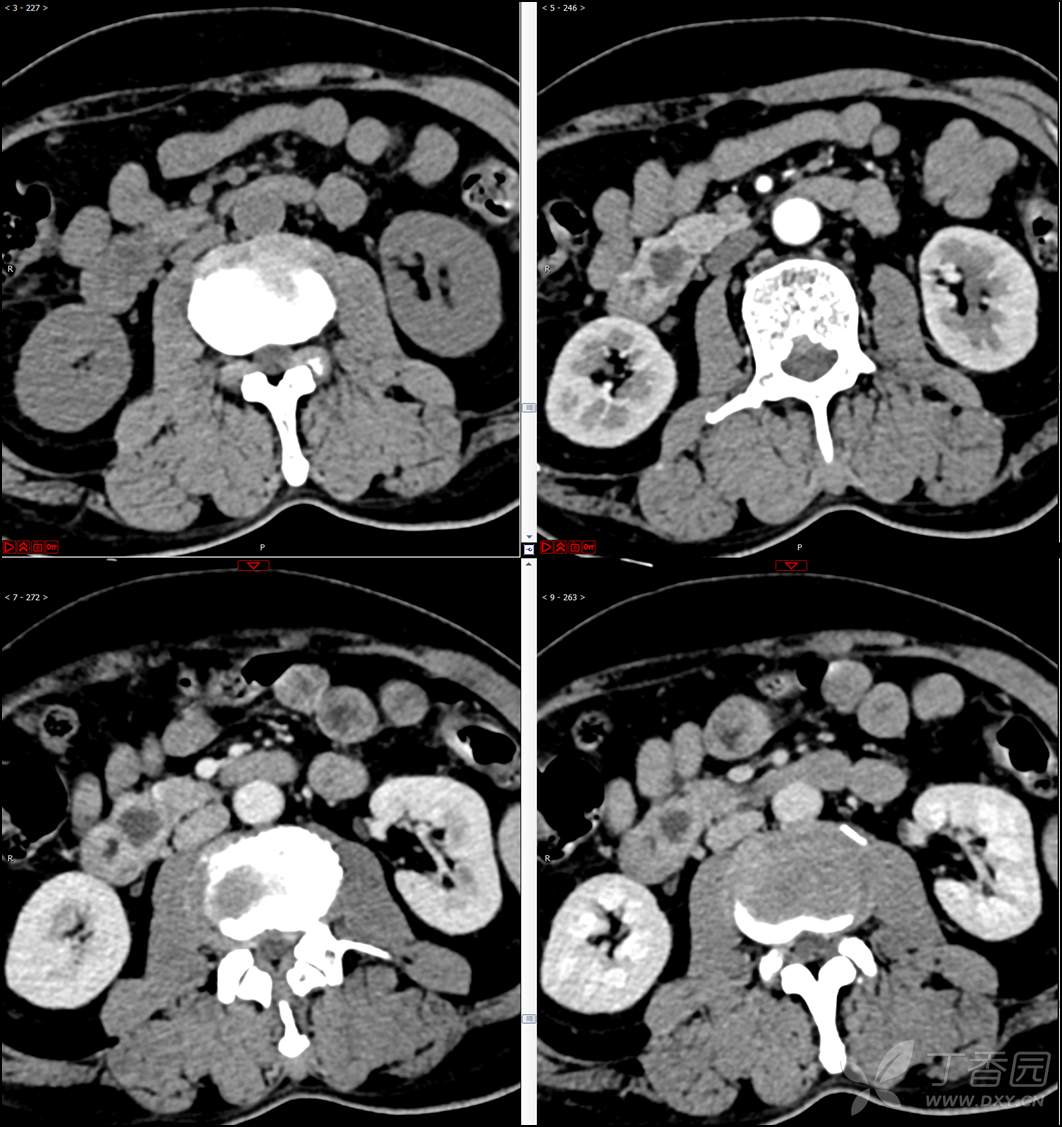

【影诊笔记521】老年男性,黑便就诊,请分析~『回帖即可查阅答案』

患者年龄:67岁

主诉:黑便1周。

现病史:患者1周前无明显诱因出现黑便伴头晕、心慌,无胸闷、胸痛,后仍间断黑便,2022-10-27就诊于某市中医院,行胃镜检查示:十二指肠溃疡伴出血,给予止血、抑酸等对症治疗,效果欠佳。今为行进一步治疗就诊于我院急诊,门诊完善新型冠状病毒核酸检测后以“十二指肠溃疡伴出血”收入我科。患者自发病以来,神志清,精神可,未进食,睡眠可,小便未见异常,黑便,近期体重无明显增减。